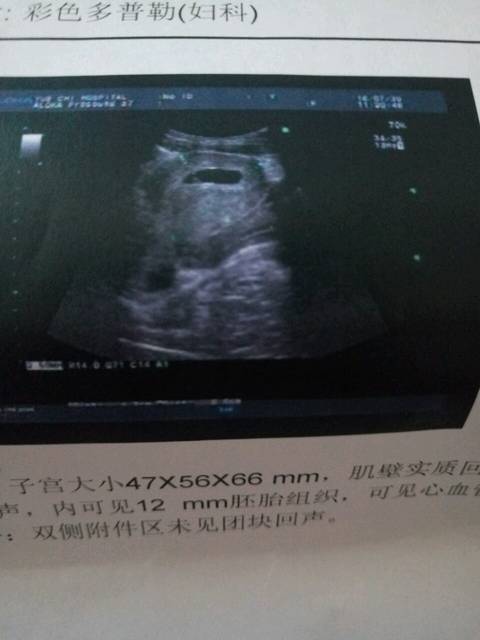

60天孕囊图男孩,60天胎儿的样子图片

看看孕囊是男孩还是女孩

孕囊看男女